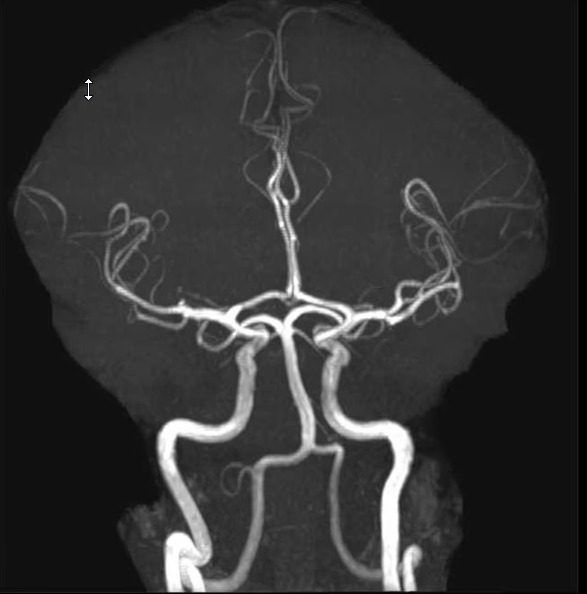

血管和脑卒中影像

- 脑卒中影像 — 快速准确判读

- 动脉瘤和血管畸形诊断

- 血管神经放射学专业知识

血管神经放射学